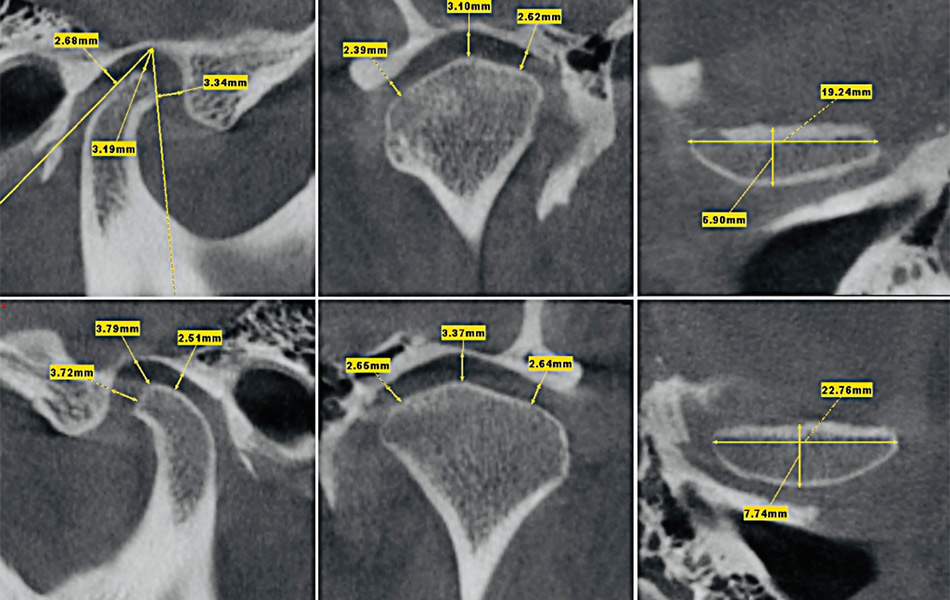

- Рентгеновские снимки (КТ, ОПТГ) суставов с описанием.

В стоматологии 32Дентал диагностика заболеваний височно-нижнечелюстного сустава проходит на современном оборудовании. Наш гнатолог проводит:

- Современная диагностика с 3D-моделированием;